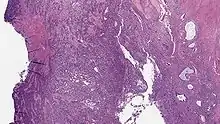

Undifferentiated uterine sarcoma

Endometrial Stromal Sarcoma, High-Grade

Undifferentiated uterine sarcoma, or undifferentiated (high-grade) endometrial stromal sarcoma, does not resemble normal endometrial stroma and behaves much more aggressively, frequently metastasizing. The differential includes leukemia, lymphoma, high-grade carcinoma, carcinosarcoma, and differentiated pure sarcomas.

Microscopy

• Monotonous ovoid cells to spindly cells with minimal cytoplasm.

• Prominent arterioles. Angiolymphatic invasion common.

• Up to 10-15 mitotic figures per 10 HPF in most active areas.

• Tongue-like infiltration between muscle bundles of myometrium.

• May exhibit myxoid, epithelioid and fibrous change.

• May have foam cells or hyalinization in the stroma.